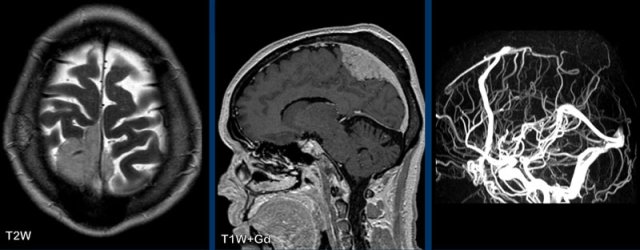

These examples show the advantage of FLAIR+Gd over T1W+Gd in a patient with lung cancer with cerebral metastases and carcinomatous meningitis.

Images

The FLAIR-image better shows the leptomeningeal enhancement around the pons (yellow arrow) and in the cerebellar foliae (black arrowheads).

Gyral pattern

The gyral pattern of enhancement is enhancement of the

cortex, most frequently seen in ischemia as a result of reperfusion during the healing

phase in subacute and acute ischemia

This can be caused by

luxury perfusion and/or cortical laminar necrosis.

Another cause of gyral enhancement is the vasodilatation phase of migraine headache and posterior reversible encephalopathy syndrome (PRES).